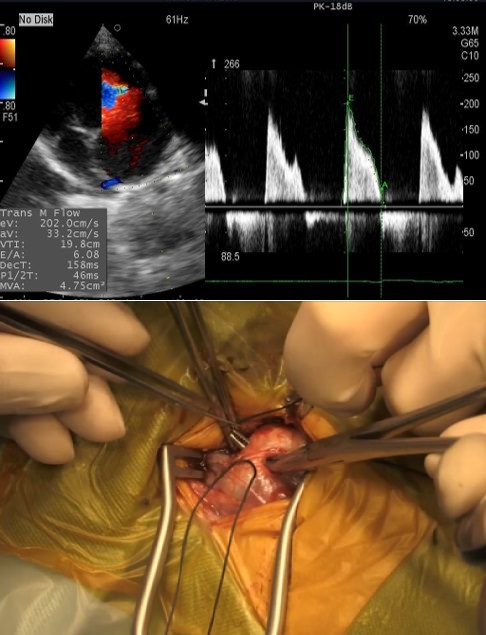

犬猫の心臓 -